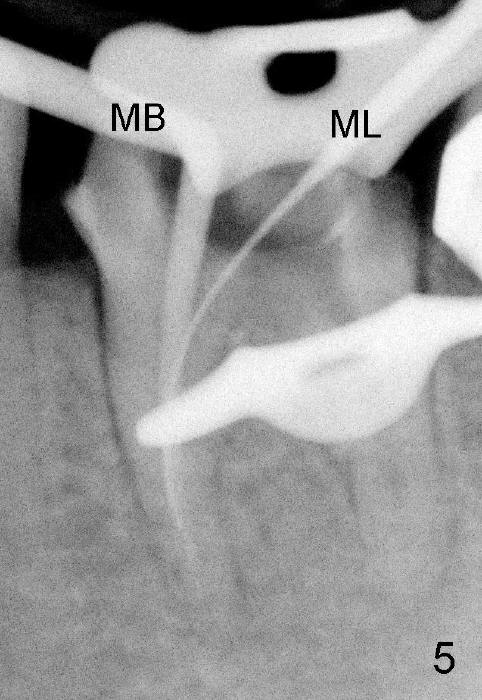

第一第二磨牙牙冠连在一起(图一;*:第二磨牙牙冠远中边缘坐在银汞充填物上),首先除去第一磨牙牙冠和冠髓腔松软充填物,后者有若干年久违丁香油气味,很容易找到远中颊舌侧(DB, DL)根管口,扩大也没什么问题(直到30/.06)。扩大针容易插入近中颊侧根管(MB),但是根尖三分之一有些阻塞,近中舌侧根管(ML)冠三分之一就阻塞,说明断针在舌侧根管,用Piezo超声波和diamond tip扩大近中舌侧根管口,也使用二号Gates-Glidden,然后使用C6, 8 扩大针慢慢地通过断针(bypass),最困难却是根尖三分之一阻塞部分(颊舌侧,尤其是舌侧),可能是断针原因。

近中根管扩大麻烦,只能慢慢来,逐渐失去working length,X光片证实(图五:MB:30/.06主牙胶尖; ML:十号扩大针),之后继续努力,向根尖进军。近中舌侧根管主要使用hand files,直到三十号,尽量往侧壁拉,让断针松弛,最后利索通过rotary file 30/.06一次,充填前再拍摄一张根尖片,希望无意中断针被冲洗出来(病人期待能把断针取出,她胆小,好不容易下定决心重做根管治疗),结果白日做梦,断针还在原处(图六),偶尔能取出自己造成断针,这次却不行,反正丑媳妇不怕见公婆,在二点五倍loops下,断针始终看不见。最后完成根管充填(四个根管都用30/.06主牙胶尖)和buildup(图七),充填好像不尽人意,这时精疲力竭,好在病人还感激,接着制作临时牙冠,打发病号。术后一两天病人还有些疼痛,只好观察,后来把她忘却。今天术后两周她突然回诊所,昨天把临时牙冠咬断(图八),我们重做临时牙冠,用永久性粘固粉,她准备明年做两个牙冠,想充分使用牙科保险钱。最振奋人心的是她张口痛完全消失,看样子术前没有TMD,虚惊一场。